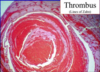

interdifitating ares of pink(platelets) and red(RBCs) found ONLY IN THROMBI FORMED BEFORE DEAD

LINES OF ZAHN